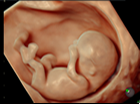

4D 超音波診断エコー

当クリニックで導入している最新式の3D/4Dエコー検査機は お腹の中の赤ちゃんの背伸びをしたりあくびをしたり指しゃぶりをしたり等の様子をリアルタイムに立体画像で見ることが可能です。

映像はSDカードに記録していきます。

お子様の胎内での成長過程を このすばらしい画像で記念に残してあげて下さい。

尚、赤ちゃんの姿勢や向きによってお顔などが十分に見られない時もありますのでご了承下さい。

- 最新機種で最上位機種の産婦人科向け超音波画像診断装置「Voluson E10」を導入致しております。

リアリティのある透明感と立体感を実現して、命の躍動をクリアに描き出します。